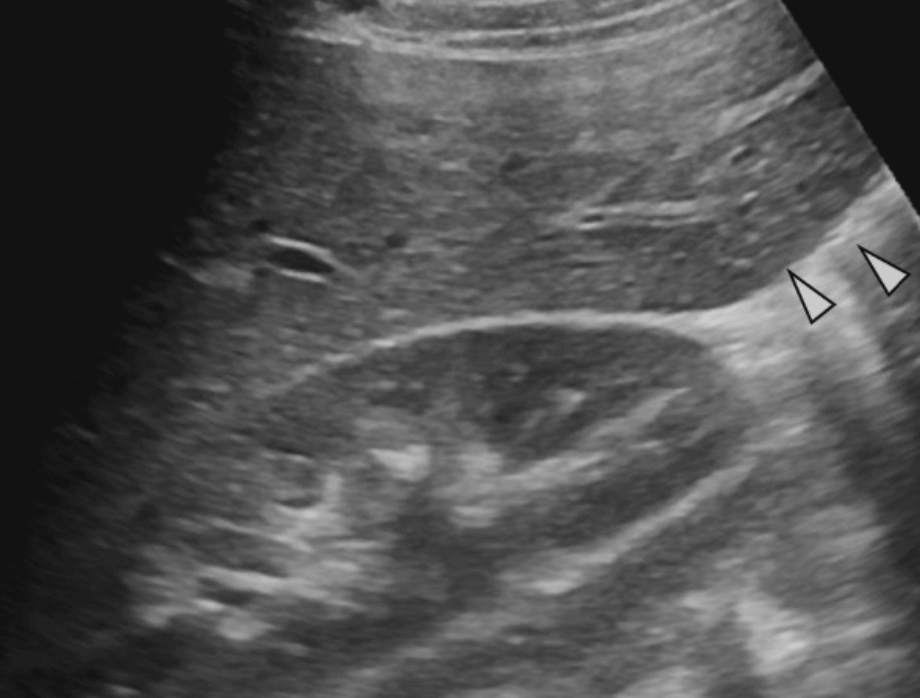

1. Riedel's lobe

Riedel's lobe 간우엽이 소혓바닥처럼 길고 두껍게 도출되어 장골극까지 하강하는 선천적 정상변이이다. 주로 여자에서 보인다.